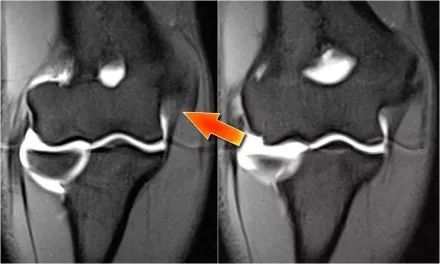

下面的图我们看到UCL的两个连续冠状图像。在近端部分(箭头)看到一些高信号是正常的。注意它是如何牢固地附着在崇高的结节上并将其与下一个图像进行比较。

请记住,UCL应该非常紧密地附着在崇高的结节上。在下面这种情况下它没有,所以即使在这两个图像上你也可以看出它有完全的撕裂。请注意,崇高结节中存在一些骨髓水肿。